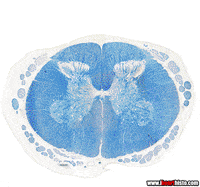

nervous system anatomy GIFNeuro GIF by American Academy of NeurologyMental Health Doctor GIF by I Heart GutsHuman Brain GIF by The University of MelbourneBrain Neurology GIF by The Explainer StudioNervous Human Body GIF by Team KennedyMedical School GIF by American Academy of Neurologyneuroscience neurology GIF by PBS Digital StudiosHuman Brain Brains GIF by The Brain Aneurysm Foundationblack and white vintage GIF by Okkult Motion Picturesbrain cgi GIF by Harvard Medical Schooloffice building GIF by South Park black and white vintage GIF by Okkult Motion Pictures